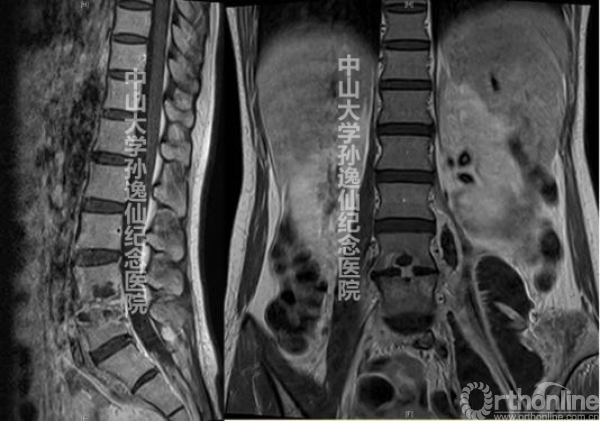

患者入院后完善相关检查,腰椎过伸过曲位X线片提示L4椎体I度前滑脱,腰椎MR提示L4/5椎间盘突出,腰椎CT未发现峡部裂等异常(图1)。骨密度检查中该患者的腰椎T值为-2.9,提示骨质疏松改变。结合患者病史及相关检查结果,我们拟定的手术方案为L4/5OLIF联合L4-5经皮椎弓根钉棒内固定术。

图1:腰椎过伸过曲位X线片提示L4椎体I度前滑脱,腰椎MR提示L4/5椎间盘突出